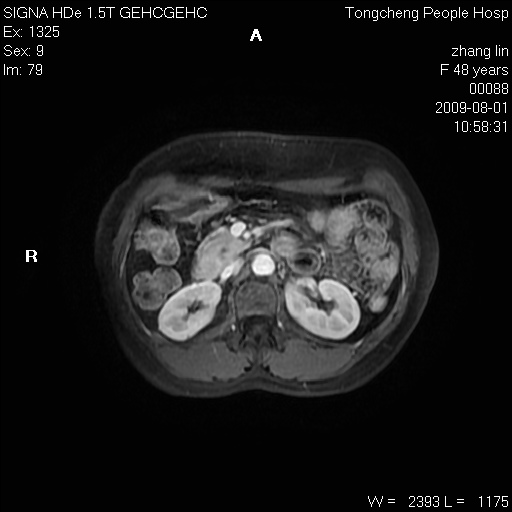

女,48岁。健康体检,彩超发现右肾占位性病变。平素健康。

临床诊断:右肾占位性病变,性质待定(囊肿?肿瘤?)。

上中腹部mr平扫+增强扫描,图像如下:

右肾上极见一类圆形病灶,t1wi呈等信号t2wi呈等高混杂信号,三期增强无强化,边界清---考虑囊肿出血。

同反相位均表现为等信号,病变无强化,考虑含蛋白的囊肿可能,弥散加权相或许有些帮助,

慢性胆囊炎